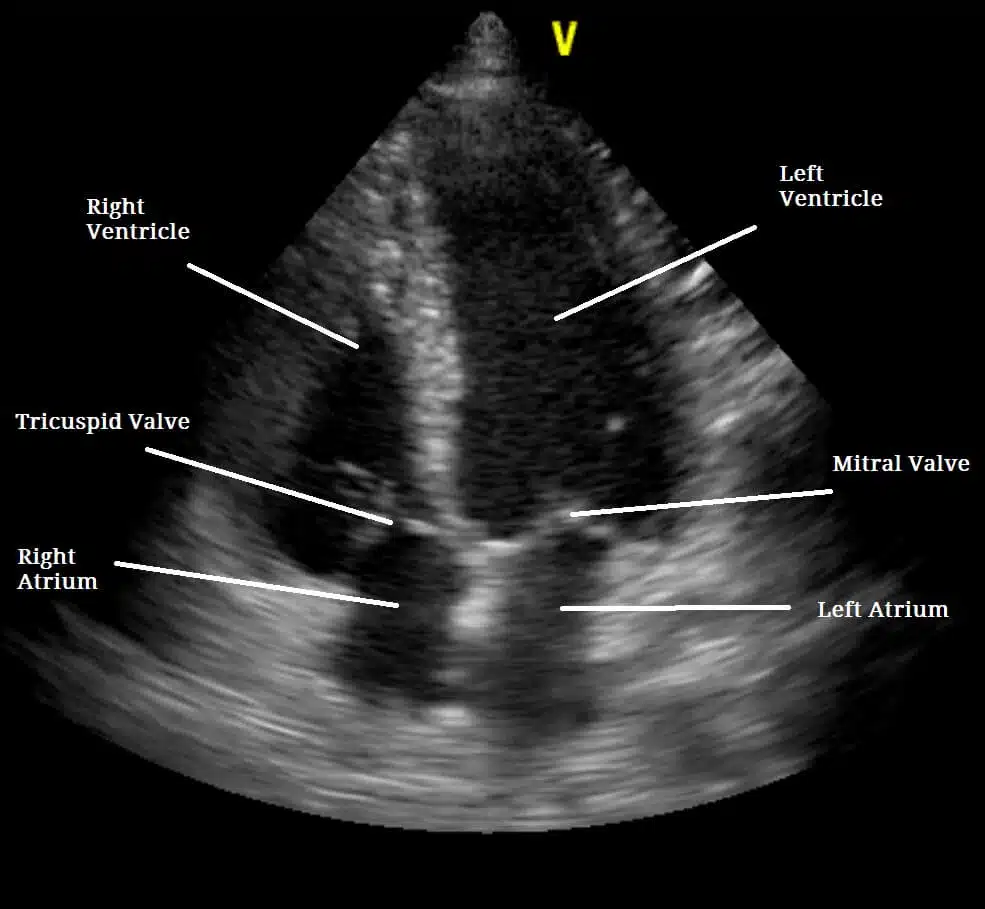

Echocardiography, also known as echo and echocardiogram, is a painless test used to diagnose heart abnormalities such as damage to the heart tissue from heart attack or poorly functioning heart valves. Echocardiography uses ultrasound waves to visualize the heart. These waves echo off the heart. They can display the shape, size and motion of the heart’s atria, ventricles and valves. Echocardiography can also show the flow of blood through the heart.

This diagnostic test is used to find probable certain cardiovascular diseases. Echocardiography is one of the most widely used tests to diagnose heart disease. Echocardiography can provide plenty of helpful data, including the size, and shape of your heart, the location and extent of any damage to the heart’s tissues and its pumping strength.